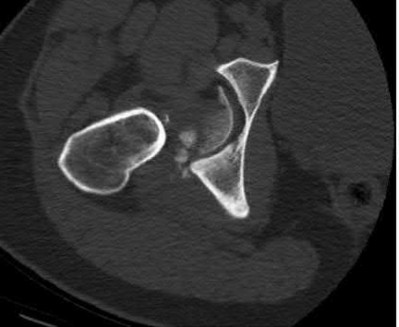

Question 2:

A 28-year-old male sustains a severe hyper-dorsiflexion injury to his ankle in a motor vehicle accident, resulting in a Hawkins Type III talar neck fracture. Which of the following arteries provides the predominant blood supply to the body of the talus, placing it at significant risk for avascular necrosis in this injury?

Correct Answer: Artery of the tarsal canal

Explanation:

The artery of the tarsal canal, which is a branch of the posterior tibial artery, provides the dominant blood supply to the talar body. In a Hawkins Type III fracture (talar neck fracture with subtalar and tibiotalar dislocation), the blood supply from the artery of the tarsal canal, the artery of the sinus tarsi, and capsular vessels are disrupted, leading to an avascular necrosis (AVN) rate approaching 100%.